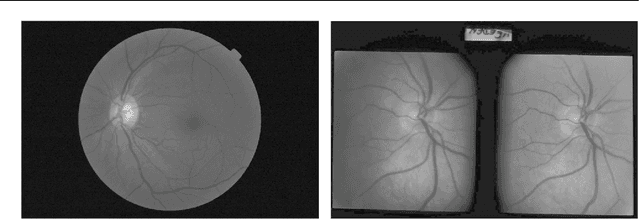

Objectives: To evaluate the performance of a deep learning based Artificial Intelligence (AI) software for detection of glaucoma from stereoscopic optic disc photographs, and to compare this performance to the performance of a large cohort of ophthalmologists and optometrists. Methods: A retrospective study evaluating the diagnostic performance of an AI software (Pegasus v1.0, Visulytix Ltd., London UK) and comparing it to that of 243 European ophthalmologists and 208 British optometrists, as determined in previous studies, for the detection of glaucomatous optic neuropathy from 94 scanned stereoscopic photographic slides scanned into digital format. Results: Pegasus was able to detect glaucomatous optic neuropathy with an accuracy of 83.4% (95% CI: 77.5-89.2). This is comparable to an average ophthalmologist accuracy of 80.5% (95% CI: 67.2-93.8) and average optometrist accuracy of 80% (95% CI: 67-88) on the same images. In addition, the AI system had an intra-observer agreement (Cohen's Kappa, $\kappa$) of 0.74 (95% CI: 0.63-0.85), compared to 0.70 (range: -0.13-1.00; 95% CI: 0.67-0.73) and 0.71 (range: 0.08-1.00) for ophthalmologists and optometrists, respectively. There was no statistically significant difference between the performance of the deep learning system and ophthalmologists or optometrists. There was no statistically significant difference between the performance of the deep learning system and ophthalmologists or optometrists. Conclusion: The AI system obtained a diagnostic performance and repeatability comparable to that of the ophthalmologists and optometrists. We conclude that deep learning based AI systems, such as Pegasus, demonstrate significant promise in the assisted detection of glaucomatous optic neuropathy.